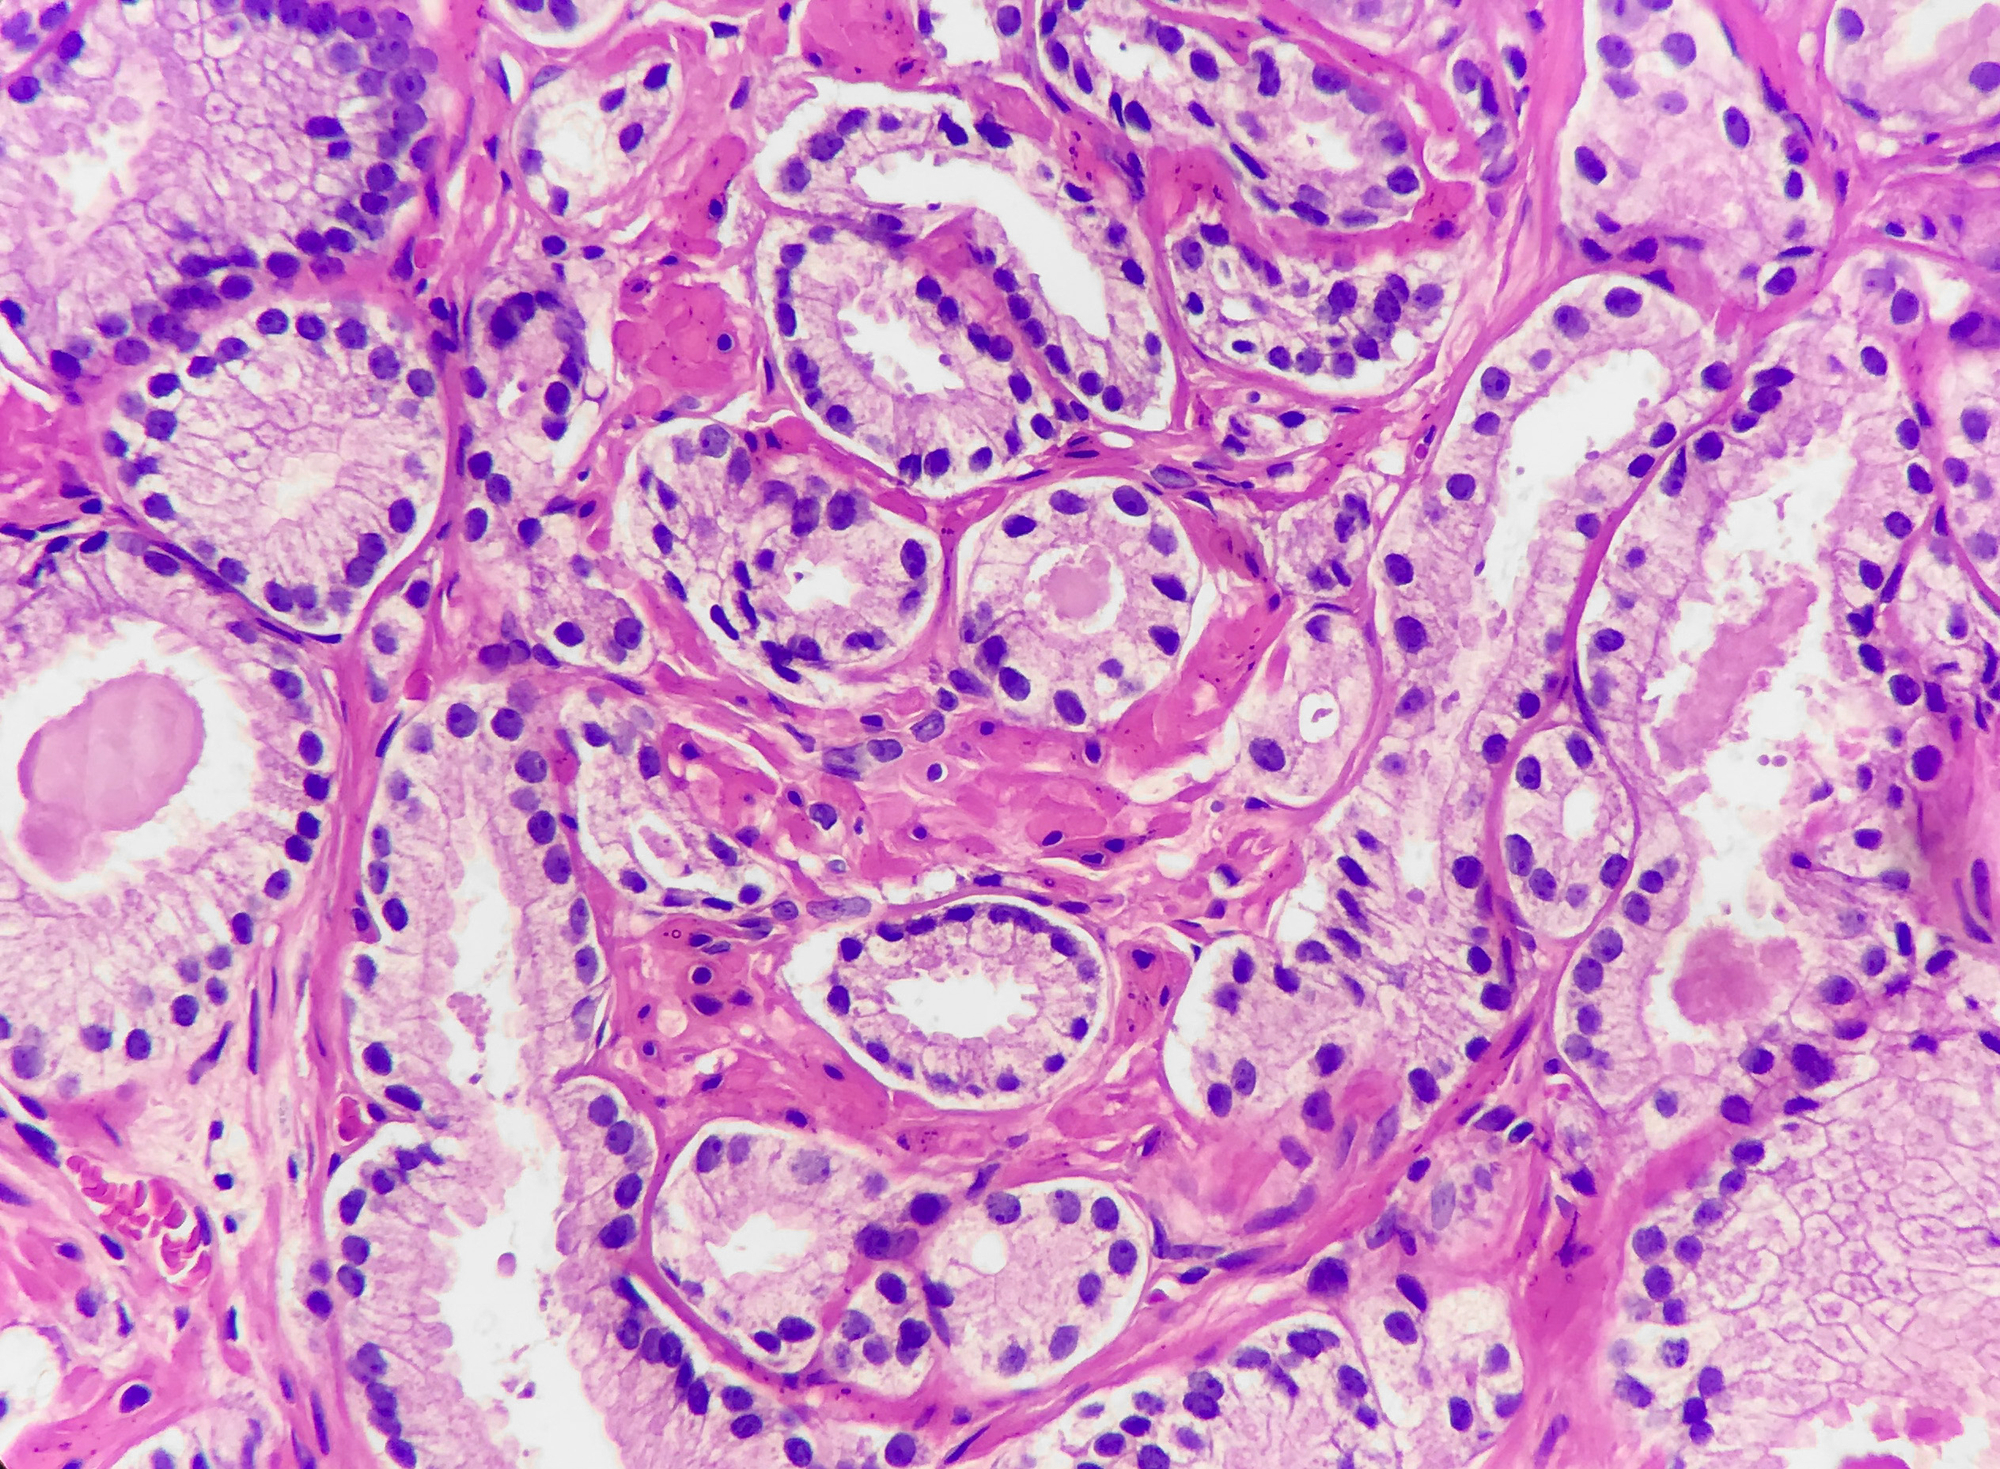

Our specialists have extensive knowledge and experience of these genitourinary and urological cancers. Each expert contributes their unique insight to ensure you get the whole picture of your condition and the most effective treatment strategies.